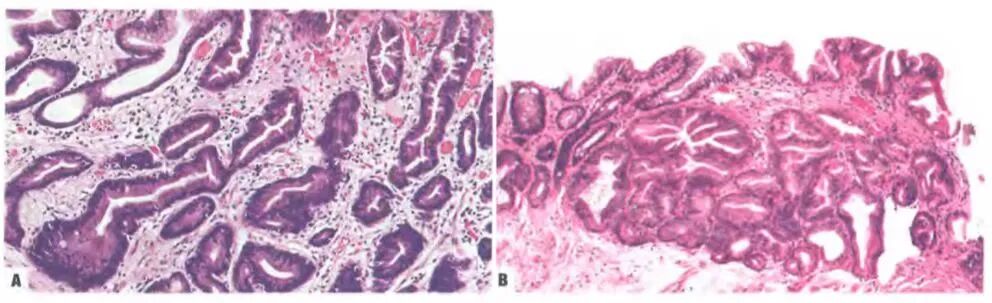

肠型胃黏膜异型增生——A:低级别异型增生,高柱状的细胞分化呈肠型细胞,细长的核位于细胞基底;B:高级别异型增生,高柱状的细胞,细胞核极性消失。(属普通型异型增生,细胞异型性低,但结构不典型性明显)